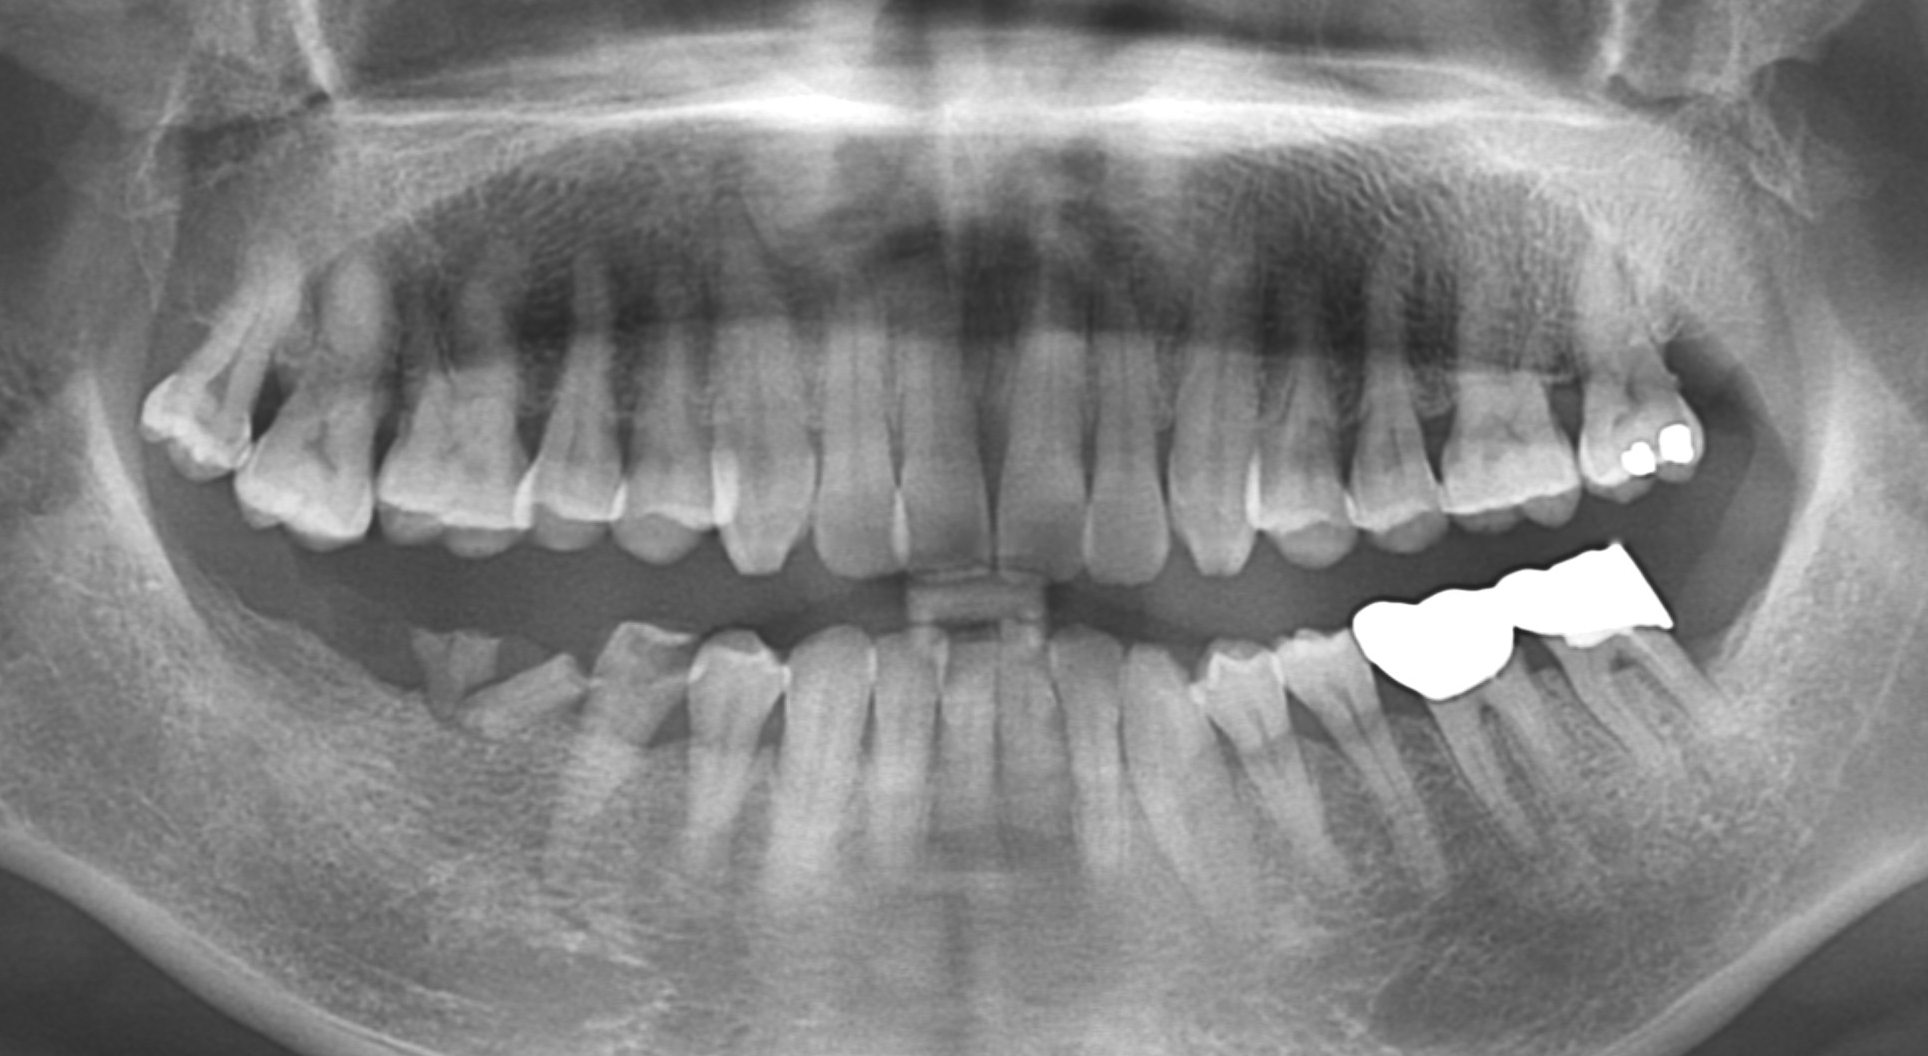

[임플란트] 제목 : 하악구치부

임플란트 및 보철치료